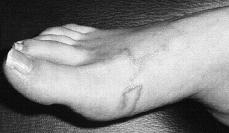

Paciente con antecedente reciente de un viaje a Méjico que llegó a nuestra consulta para valorar unas lesiones cutáneas en ambos pies, diagnosticadas y tratadas previamente como eccema dishidrótico sin notar mejoría. Se apreciaban lesiones vesiculoampollosas en planta de varios dedos de ambos pies junto con otras lesiones eritematosas lineales, serpentiformes y que hacían un discreto relieve, localizadas en dorso y caras laterales de ambos pies (Fig. 1). La paciente se quejaba de intenso prurito y refería que «dichos túneles» avanzaban de un día para otro.

FIG. 1.--Caso 1. Lesiones vesiculoampollosas en los dedos y serpiginosas en la planta.